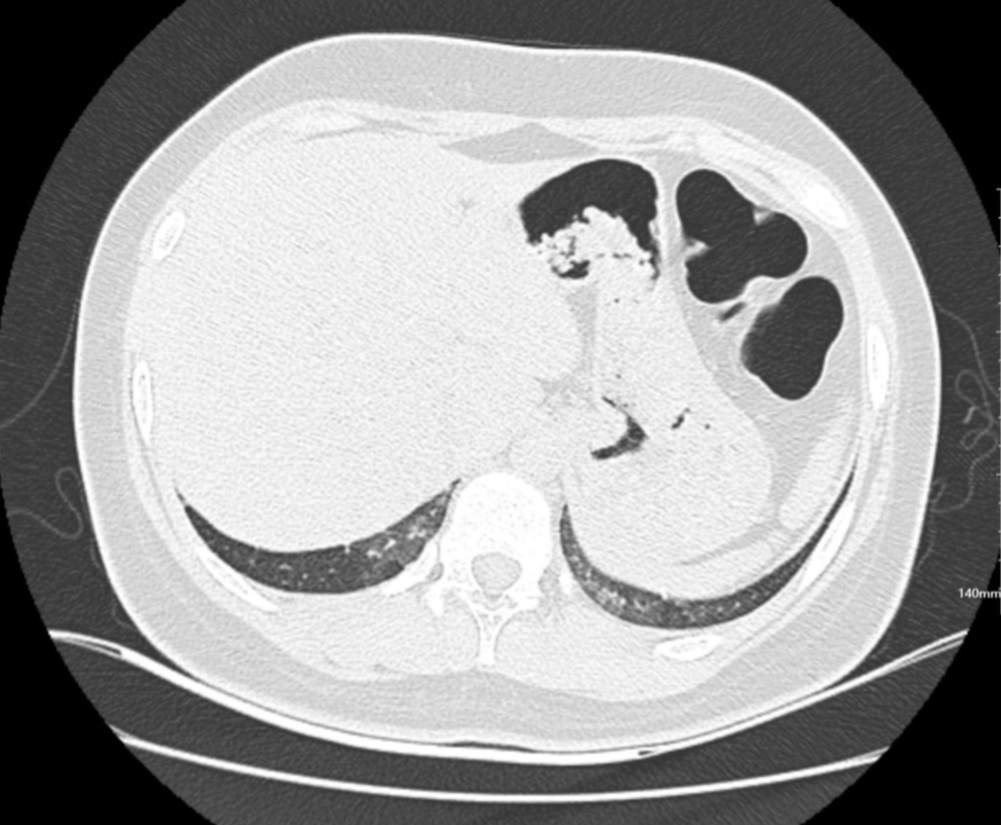

肺部CT:

百日咳肺炎CT 表现

支气管血管束增粗且伴 < 2 个肺叶的磨玻璃密度影, 多提示为单纯性百日咳肺炎。(下图:支气管血管束增粗, 两肺下叶基底段少许磨玻璃密度影)

如出现肺内支气管血管束增粗, 伴≥3 个肺叶斑片影、亚段性实变及支气管气象时, 提示患儿病情较重,可能合并其他感染。